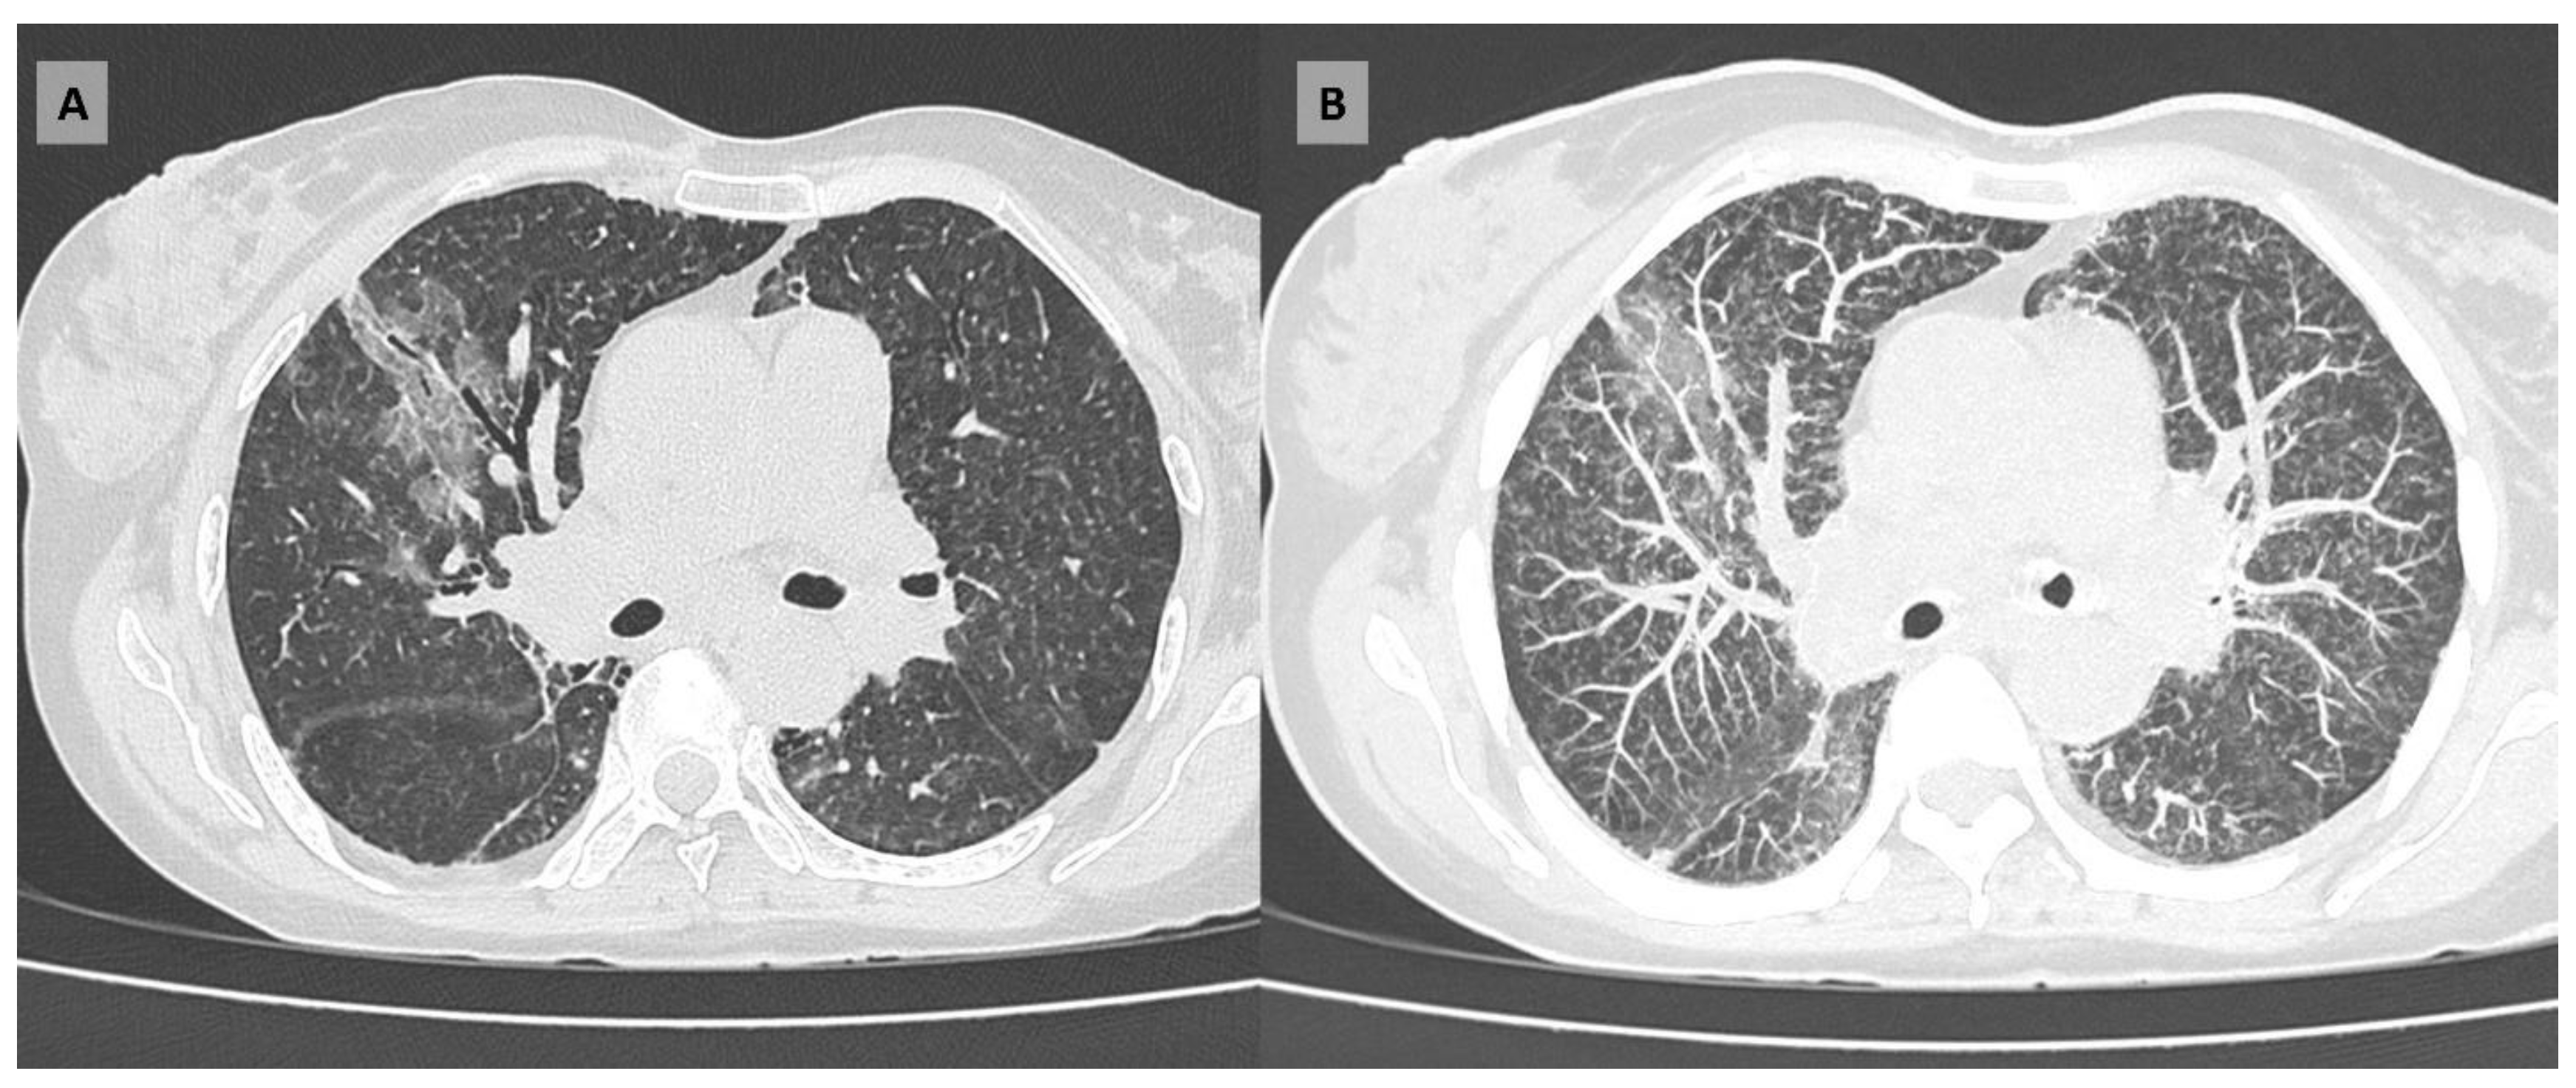

A chest X-ray revealed bilateral alveolar infiltrates, prompting the initiation of empirical antibiotic therapy with ampicillin-sulbactam (3 g qid) and clarithromycin (500 mg bid). The initial blood count showed lymphopenia (320/mcL). Additional tests showed a negative HIV result, as well as negative initial cultures. Despite treatment, the patient exhibited no clinical improvement and continued to experience fever and desaturation. A subsequent chest computed tomography scan revealed multiple randomly distributed micronodules in both lungs, along with ground-glass opacities, lymphadenopathies and subpleural areas of honeycombing (Figure 1). Given these findings, the antibiotic regimen was modified to piperacillin-tazobactam (4.5 g every six hours) on the second day of hospitalization, and a bronchoscopy with bronchoalveolar lavage (BAL) was performed. By day 7 of hospitalization, the report was received. The BAL analysis identified Pneumocystis jirovecii, leading to the initiation of trimethoprim/sulfamethoxazole at a dose of 15 mg/kg/day. Galactomannan was negative.

Additionally, it is crucial to consider the diagnostic methods specific to each infectious agent. In histoplasmosis, the most common radiological findings are diffuse or interstitial opacities, although micronodules or nodules may also be present. Furthermore, in both acute and subacute histoplasmosis, lymphadenopathy can be observed, a finding that is less common in Pneumocystis pneumonia, where the predominant manifestation is ground-glass opacity. The coexistence of combined tomographic patterns, along with the presence or absence of lymphadenopathy, as seen in this patient, underscores the necessity of considering a broad range of infectious agents in immunosuppressed individuals.[3,10]

Figure 1. Chest computed tomography (CT) images of the patient. (A) Axial CT scan showing diffuse ground-glass opacities in both lungs. (B) Maximum intensity projection image highlighting a randomly distributed micronodular pattern.